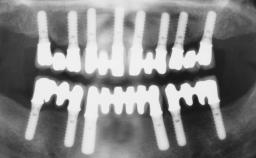

Transition from an “irrational to treat” Maxillary Dentition to a Full-Arch Segmented FDP by Early Loading of Eight Implants Placed Using the Staged Approach

The staged approach permits the transition from an “irrational to treat”dentition to a full arch implant supported restoration without any need to use a removable provisional prosthesis or to apply the immediate-placement and immediate-loading techniques.  A failing dentition is the usual indication for a staged treatment. On the other hand, the dentition should still contain many residual teeth, but with few or none of them being suitable for use as definitive abutments for a full-arch fixed restoration.This situation is usually the result of advanced periodontal disease or of the failure of an extensive fixed prosthesis.

# of Implants 8

Type of Implants One-Piece

Defining Characteristics Fully edentulous upper jaw to be rehabilitated with four or more implants

Bone Volume Deficient horizontally, allowing simultaneous augumentation